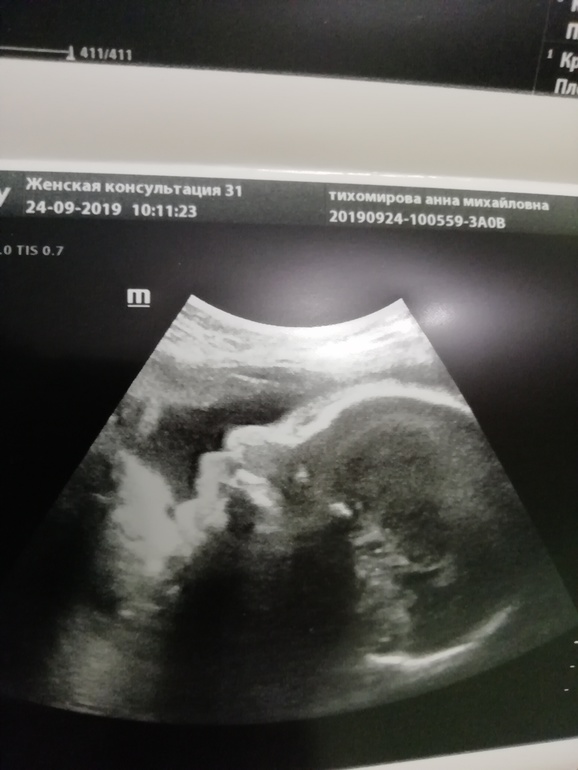

Сегодня 24.09 ходила на третий узи скриннинг.

Что имеем:

-по доплеру все отлично, кровотоки в норме

-малыш идет ровно в срок по замерам

-предполагаемый вес около 1500гр

-шейка закрыта и не укорочена

-⚠️плацента осталась в краевом предлежании, не поднялась ни на сколечко

- ❗вчера малыш лег в поперечное, как в гамаке, ему плацента видать внизу мешает встать головой нормально

Я, конечно, понимаю, что до 36 недель еще небольшой шанс на поднятие плаценты и его разворот есть, но уже и не надеюсь, потому что за всю Б плацента так и осталась в краевом предлежании. Не хочу кесарево.

Контрольное узи назначено на 33-34 недели.